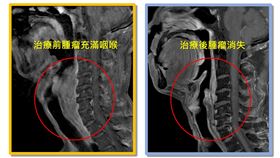

下咽腫瘤塞滿咽喉 男進食呼吸都困難

50多歲病人因下咽腫瘤遲遲不治療,腫瘤擠滿喉部到無法...